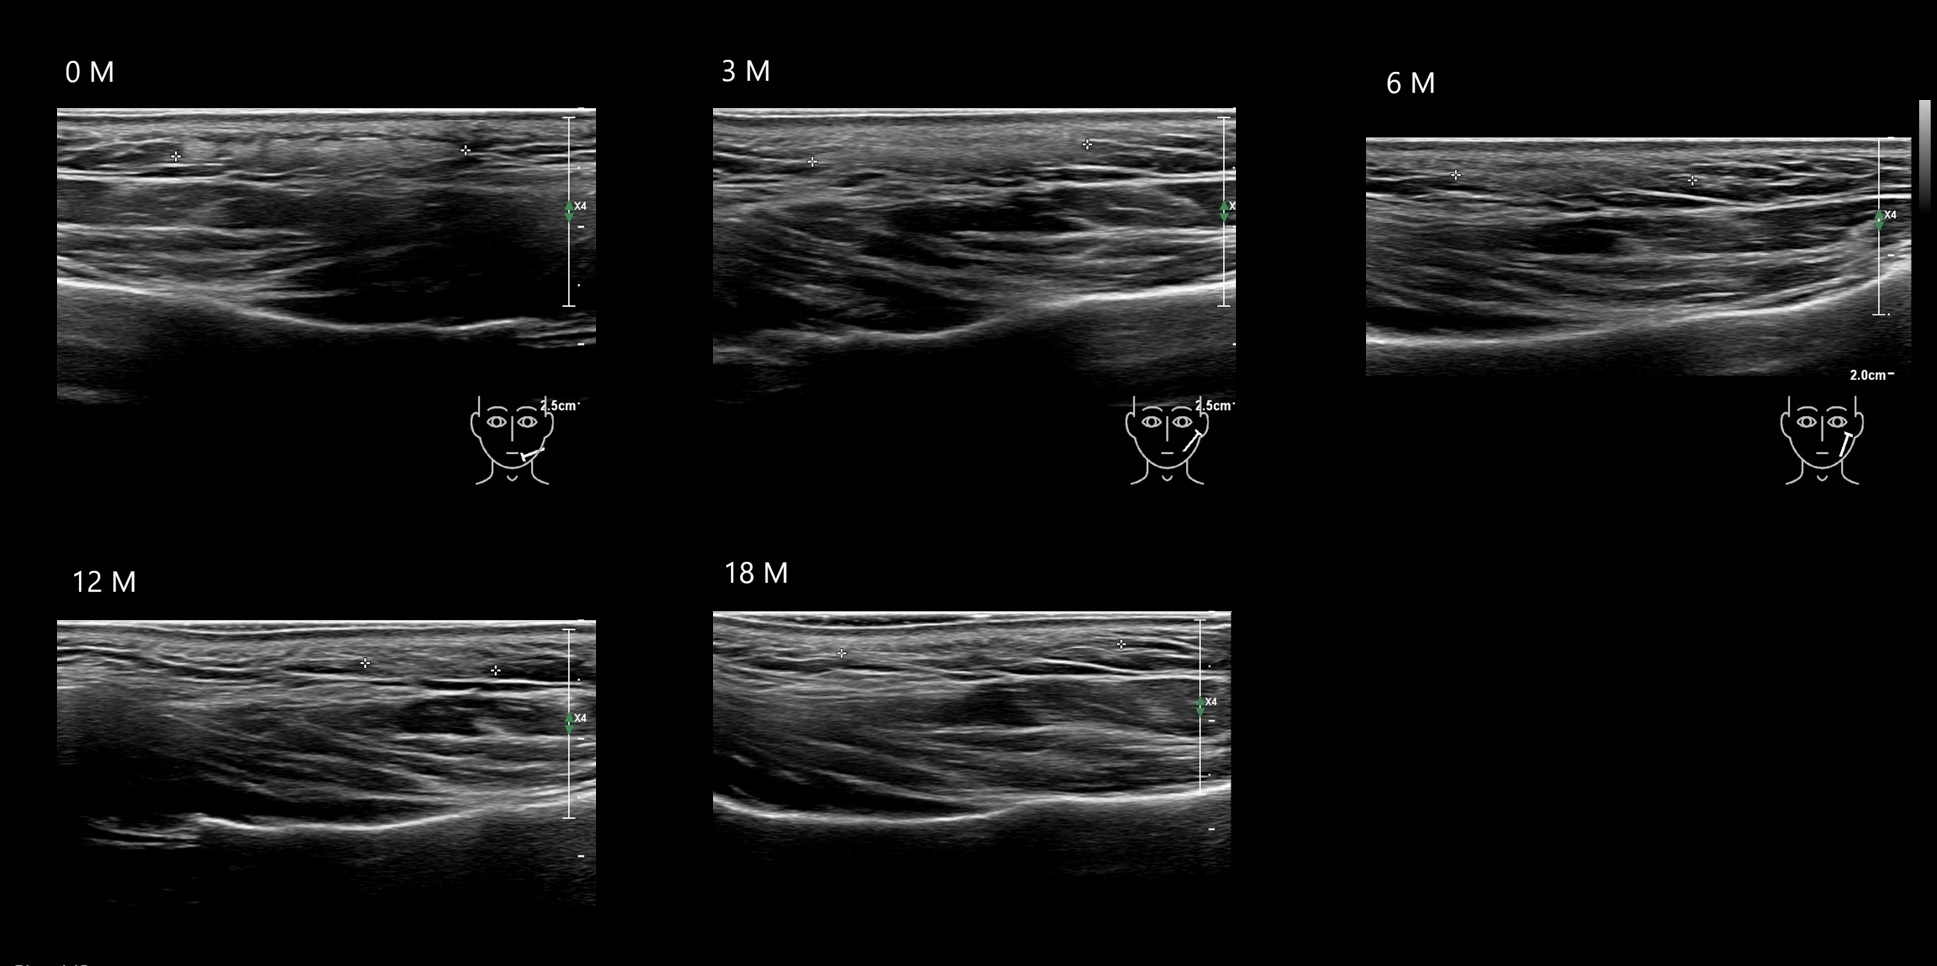

Fillers

Draw in the second image below where the fillers are located. To check if your answer is correct, swipe the first image to the right.